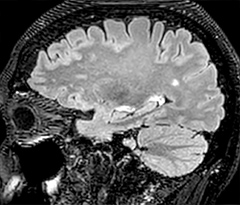

The abbreviated MS protocol for brain is only around 9 minutes, so in case of suspected multiple sclerosis, one or two more advanced sequences may be added, such as PSIR (phase sensitive inversion recovery) or susceptibility-weighted sequences to help us make more confident diagnoses in these inflammatory cases.

In this example, the optional 3D multishot susceptibility weighted sequence with 0.6 mm isotropic voxels is 2 lesions with a central vein sign (arrows) and one lesion with a phase-rim sign (arrowhead). The total scan time, including SmartBrain and axial PD/T2 3mm, is 11:10 min. and is 18:30 min. with the optional 3D PSIR and 3D SWI multishot included.

“In multiple sclerosis patients, we increasingly include a multishot susceptibility sequence [3] in our routine cases, thanks to the shorter scan times. Our abbreviated MS protocol for brain is around 8 to 9 minutes, so we can ask for one or two additional sequences to visualize the central veins, or to get an additional contrast to better depict posterior fossa lesions. In cases of white matter lesions of unknown significance on FLAIR images, for example when we see high signal hyperintensities in the brain, we can add on more advanced sequences such as PSIR (phase sensitive inversion recovery) or susceptibility-weighted sequences to help us in distinguishing between MS and nonspecific or vascular abnormalities in these inflammatory cases.”